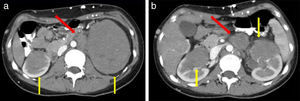

Extensión retroperitoneal contiguaEs la segunda forma de presentación, con un 11-25% de los casos1,14. Generalmente, los pacientes evidencian una masa retroperitoneal voluminosa, hipodensa con escaso realce poscontraste, que infiltra el parénquima renal a través de la cápsula o el hilio, envolviendo las arterias y las venas sin producir trombosis. El atrapamiento de los uréteres puede causar hidronefrosis1,2,12(fig. 2).

El diagnóstico diferencial incluye metástasis de adenocarcinoma de próstata, colon o tumor primario desconocido6.